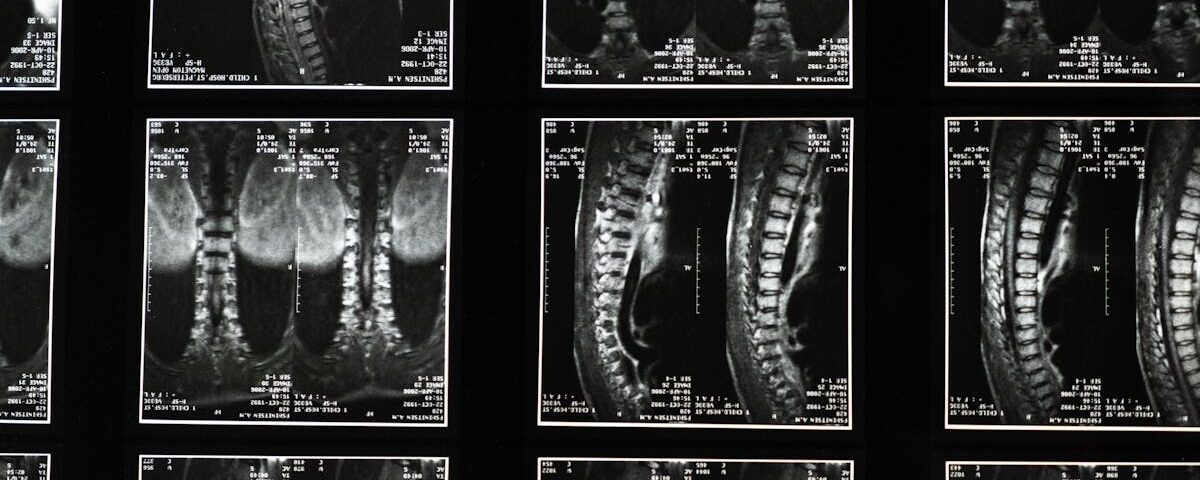

La décompression spinale est une technique thérapeutique non invasive conçue pour soulager les douleurs associées aux pathologies de la colonne vertébrale, comme les hernies discales ou les douleurs lombaires. Elle utilise un dispositif spécialisé pour réduire la pression exercée sur les disques intervertébraux et les nerfs de la colonne. Ce traitement a pour but d’améliorer la circulation sanguine et de favoriser ainsi la guérison des tissus affectés.

La décompression spinale a pour objectif de réduire la pression sur les disques intervertébraux et les nerfs de la colonne vertébrale en créant un espace entre les vertèbres. Cela permet à de nombreux patients qui souffrent de conditions comme les hernies discales ou la sténose spinale de retrouver mobilité et confort sans avoir recours à des interventions chirurgicales invasives. Cependant, des scepticismes demeurent concernant son efficacité réelle.